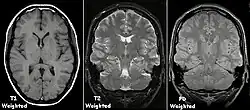

Exemplos de exames de ressonância magnética ponderada T1, ponderada em T2 e ponderada por DP.

Cada tecido retorna ao seu estado de equilíbrio após a excitação pelos processos independentes de T1 (spin-tretice) e T2 (spin-spin) de relaxamento. Para criar uma imagem ponderada em T1, a magnetização pode ser recuperada antes de medir o sinal MR, alterando o tempo de repetição (TR). Esta ponderação de imagem é útil para avaliar o córtex cerebral, identificando tecido adiposo, caracterizando lesões focais e, em geral, para obter informações morfológicas, bem como para imagens pós-contraste. Para criar uma imagem ponderada em T2, a magnetização pode decair antes de medir o sinal MR alterando o tempo de eco (TE). Esta ponderação de imagem é útil para detectar edema e inflamação, revelando lesões de substância branca e avaliando a anatomia zonal na próstata e no útero.